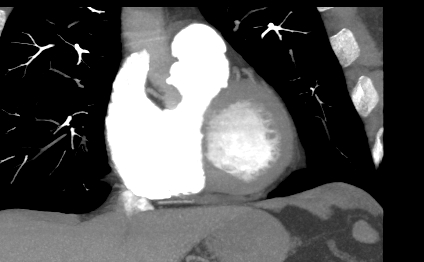

Компьютерная томография сердца является высокотехнологичным лучевым методом исследования, который позволяет оценить строение и особенности анатомии камер сердца, визуализировать состояние перикарда, коронарных артерий и восходящей части и дуги аорты.

В нашей клинике КТ сердца проводится на новейшем 128-срезовом мультиспиральном компьютерном томографе экспертного уровня TOSHIBA AQUILION CXL. Томограф послойно сканирует анатомическую область сердца, производя срезы толщиной от 0,5 мм. Методика сканирования сердца 128-срезовым КТ сканером производится с использованием перспективной синхронизации по электрокардиографии (ЭКГ).

Спиральное сканирование с ЭКГ-синхронизацией обеспечивает быстрый и непрерывный сбор данных изображений во время каждого удара сердца без каких-либо задержек. Это дает возможность сократить время сканирования, тем самым снизить лучевую нагрузку на пациента, при этом сохранить максимально возможное качество изображений.

Протокол сканирования предусматривает внутривенное болюсное контрастирование. Контрастное вещество на основе йода вводится пациенту внутривенно непосредственно во время исследования. Контраст равномерно распределяется по сосудистой системе, благодаря чему становится хорошо видна восходящая часть аорты с отходящими от нее венечными артериями и дуга аорты. По результатам обследования можно решить, нуждается пациент в проведении стентирования коронарных артерий или нет.